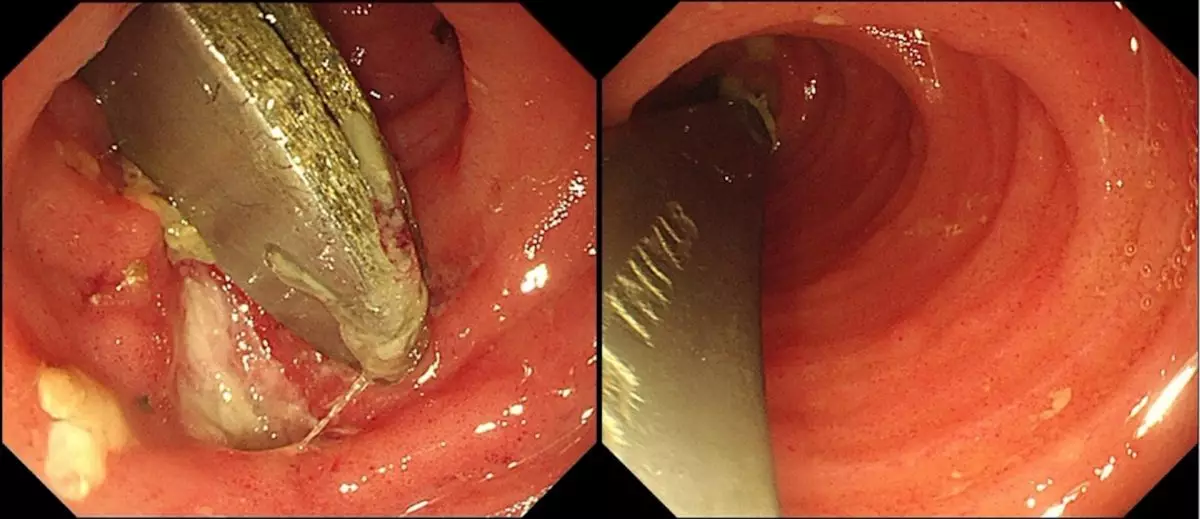

腹痛1周求診 CT揭腸道藏兩把匙羹

近日,陝西西安一名28歲張姓男子因持續腹痛一周前往求診,經電腦斷層掃描(CT)檢查後赫然發現腸道內竟藏有兩把匙羹。據南京鼓樓醫院消化內科介紹,張先生最初於西安接受檢查,CT顯示腸道內出現一條狀高密度影像。經追問病史,張先生才想起3周前曾誤吞匙羹,惟異物一直未能自然排出,最終引發腹痛不適。由於不希望接受外科手術,他經朋友介紹轉往南京鼓樓醫院求診。

匙羹卡回腸末端 黏膜潰瘍險釀穿孔

入院後,醫生為張先生再次安排CT及腸鏡檢查,確認兩把匙羹卡在回腸末端,周邊黏膜已出現潰瘍變化,隨時有腸道穿孔風險,情況相當危險。由於異物長約12CM,且位處腸腔較狹窄的小腸位置,取出難度甚高。醫療團隊經過近1小時的細緻操作,最終成功以內窺鏡將兩把匙羹完整取出,令患者免卻接受剖腹手術之苦。

醫生籲勿延誤處理 誤吞異物24小時內求醫

醫生提醒,誤吞異物在臨床上並不罕見,若未及時處理,可能引發消化道出血、穿孔等嚴重併發症。一旦懷疑誤吞異物,應盡快於24小時內求醫檢查及處理,切勿延誤,以免釀成更大風險。